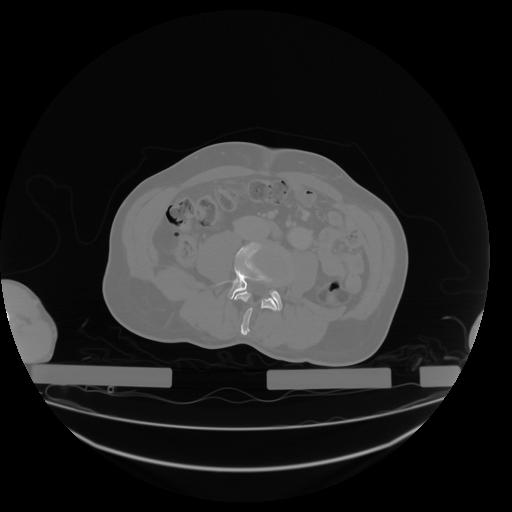

27 CUERPO,CE,Axial,3.0,CUERPO,,